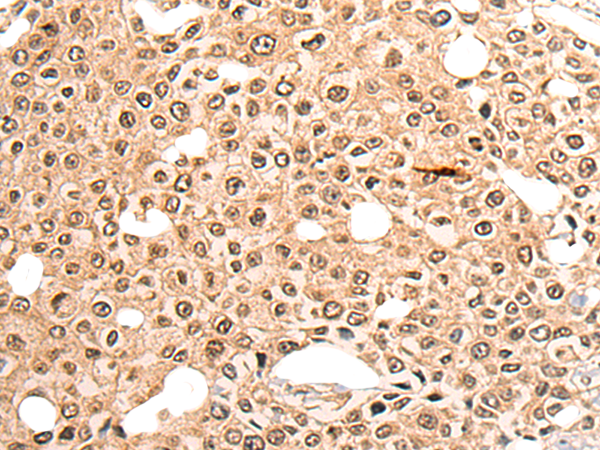

分类: 科研抗体货号: P13201别名: CNG4; CNG5; CNCA2; CNG-4; CNGB2; OCNC2; OCNCb; OCNCBETA应用: WB,IHC反应种属: Human, Mouse, Rat